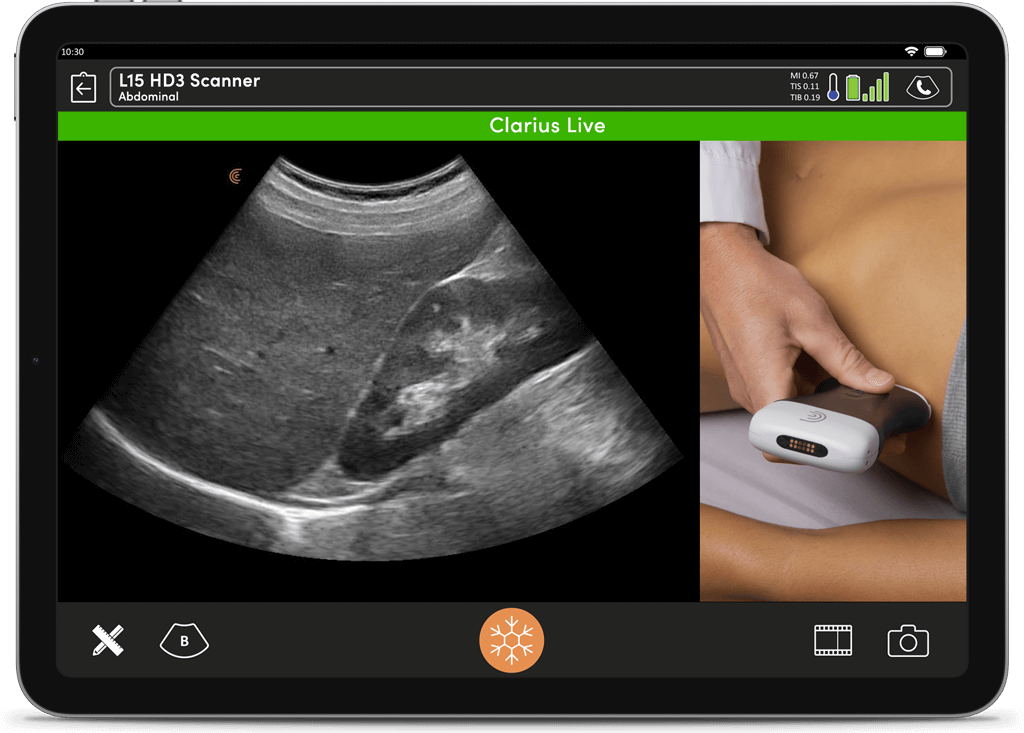

I feel more confident with my ultrasound exams since I’ve started using OB AI. I love how the AI makes the app light up when things are perfectly lined up – I can see this really helping both seasoned clinicians and those who are starting their ultrasound journey.